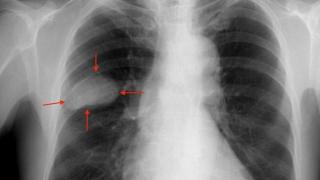

La detección temprana del cáncer de pulmón se realiza mediante TAC de baja dosis.

Sobre el cribado del cáncer de pulmón hay mucho escrito. La idea consiste en seleccionar a las personas en riesgo de desarrollar este tumor y realizarles una tomografía computarizada de baja dosis cada uno o dos años.

El TAC detectaría las primeras señales del cáncer y posibilitaría tratamientos más eficaces, incluso potencialmente curativos, en parte de los pacientes que, a día de hoy, tiene pocas opciones.